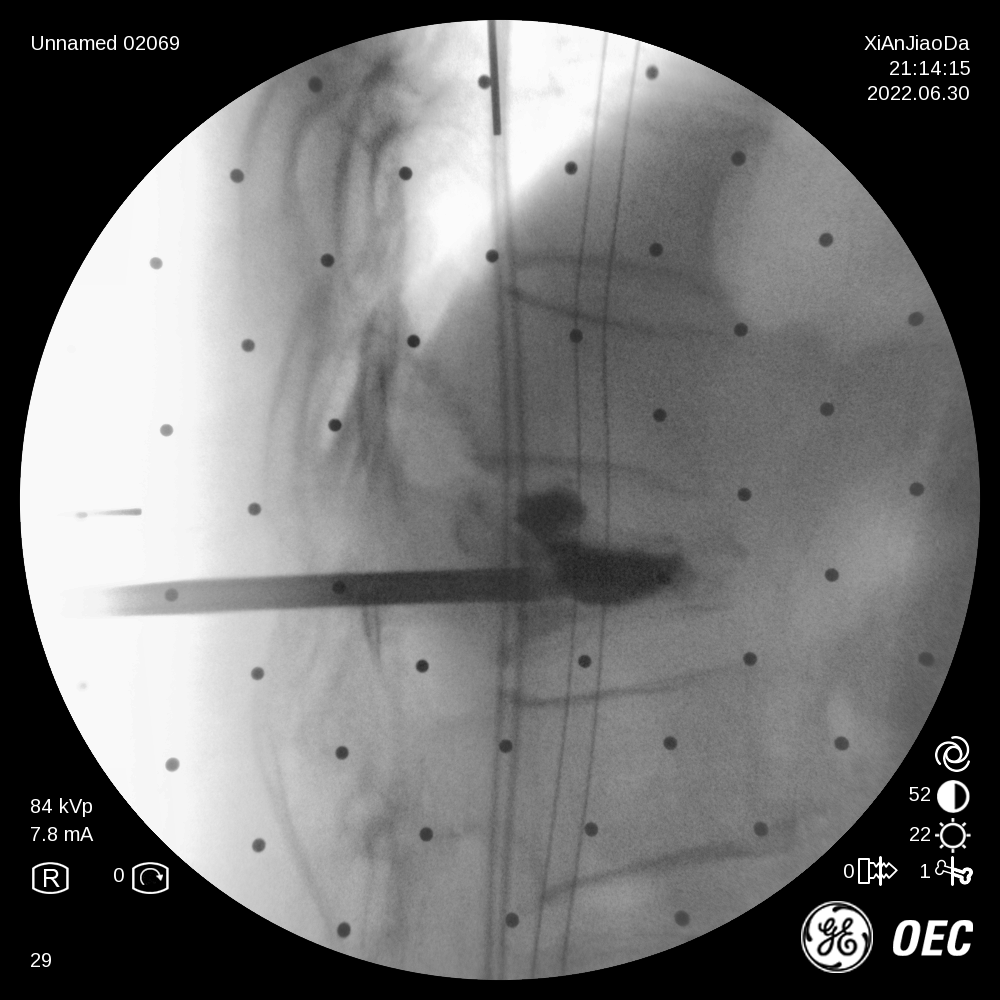

骨关节外科实施我院首例机器人辅助经皮椎体球囊扩张成形术

6月30日,骨关节外科成功为一例复杂椎体压缩性骨折病人在局麻下行机器人辅助经皮椎体球囊扩张成形术。在王坤正主任的指导下,宋金辉副主任医师、张晨副主任医师借助机器人术前规划与术中辅助,快速高效完成了该手术,...